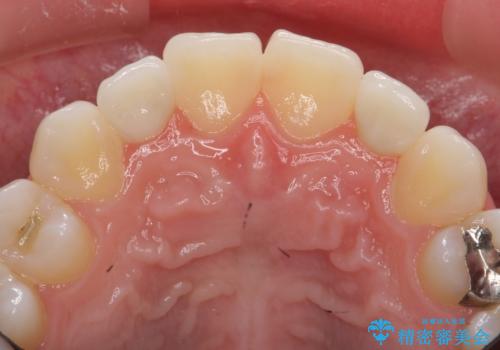

いきなりセラミックでかぶせるよりも手間をかけた分、自然な仕上がりになっています。

先に矯正治療をすることで、下の前歯を内側に入れることができ、上の歯のセラミックの幅や厚みを取ることができました。